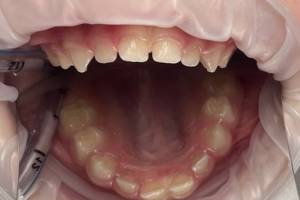

Семейная областная стоматология "Кидди Дентал" - это команда компетентных врачей, каждый из которых знает и любит свое дело. Опыт наших врачей, использование современного оборудования и надежных материалов позволят проводить лечение любой сложности.